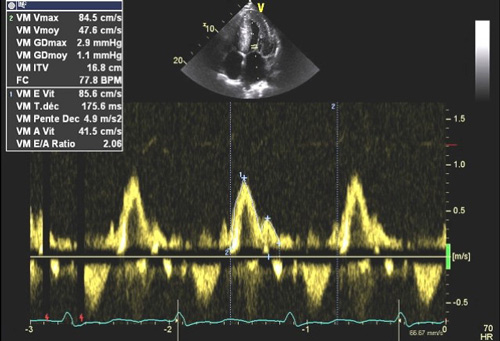

La dilatation des oreillettes est fréquente et s’associe à une dysfonction diastolique. Les pressions de remplissages VG sont souvent élevées (Figure 2) sauf à un stade préclinique chez certains patients a- ou peu symptomatiques. L’étude de la fonction diastolique ventriculaire gauche est basée sur une approche multiparamétrique intégrant le Doppler pulsé mitral, le DTI à l’anneau mitral, le volume de l’oreillette gauche (>32-34 ml/m² SC) et la Vmax du flux d’IT (>2.8 m/s) permettant également d’estimer les pressions artérielles pulmonaires (PAPS).

Figure 2 : Pressions de remplissage VG élevées souvent élevées en cas d’amylose cardiaque évolutive.

Exemple de pressions de remplissages élevées chez un patient avec amylose cardiaque : E/A >2, E/E’ moyen = 13, volume biplan indexé de l’OG > 34 ml/m² SC, Vmax de l’IT proche de 2.8 m/s